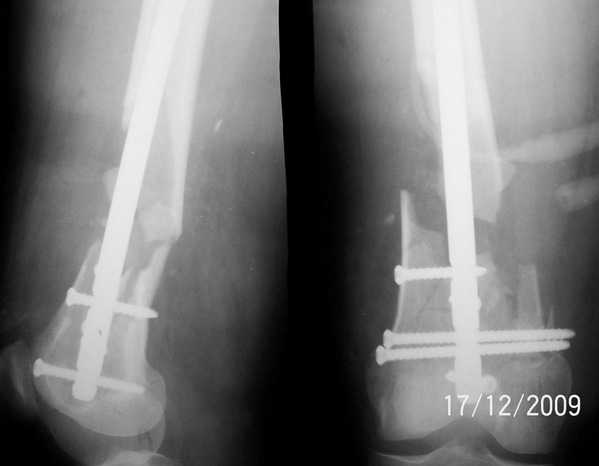

1. Открытый с дефектом кости 5 см оскольчатый внутрисуставной перелом дистального эпиметафиза бедренной кости. Величина дефекта установлена после сравнительных рентгенограмм обоих бёдер с линейкой. При поступлении выполнена ПХО раны, скелетное вытяжение за бугристость большеберцовой кости.

2. После долгих сомнений выполнена открытая репозиция перелома эпифиза бедренной кости, закрытый блокированный интрамедуллярный остеосинтез (к слову, оперативное вмешательство выполнено без применения ЭОПа). Предполагалась через 8 недель пластика костного дефекта спонгиозным аутотрансплантатом.

3. Снимок через 10 недель после операции. Имеется облаковидный регенерат. Решено от костной пластики воздержаться.

4. Через 6 месяцев имеем сросшийся перелом.

Уважаемые коллеги, прооперирована пациентка антеградным штифтом Остеомед, костная пластика не проводилась. Выбранный штифт по каналу бедренной кости на фоне отсутствия переднего кортикала в канале не центрируется. Технически неприятно, отсутствие передней и внутреннебоковой стенки до зоны мыщелков сильно затрудняло репозицию. Получилась вот такая картина. После стабилизации - очевидное повреждение ПКС и боковая нестабильность. В общем и далее будет чем заняться. Нам и в дальнейшем будет очень интересно мнение коллег.

Мне кажется, что технически всё выполнено хорошо и шансы на консолидацию перелома высокие. Безусловно, в данном случае технически более оправданным был бы выбор стержня, у которого самое дистальное отверстие расположено во фронтальной плоскости. При этом самый дистальный блокирующий винт полностью бы располагался в неповреждённых мыщелках бедренной кости и надёжно выполнял бы свою функцию. То же касалось бы и винта в сагитальной плоскости. достаточно было бы этих двух винтов. Но не всегда имеется в наличии то что необходимо. По всей вероятности, оперативное вмешательство было не из лёгких. Остаётся только поздравить коллег с решением основной задачи.